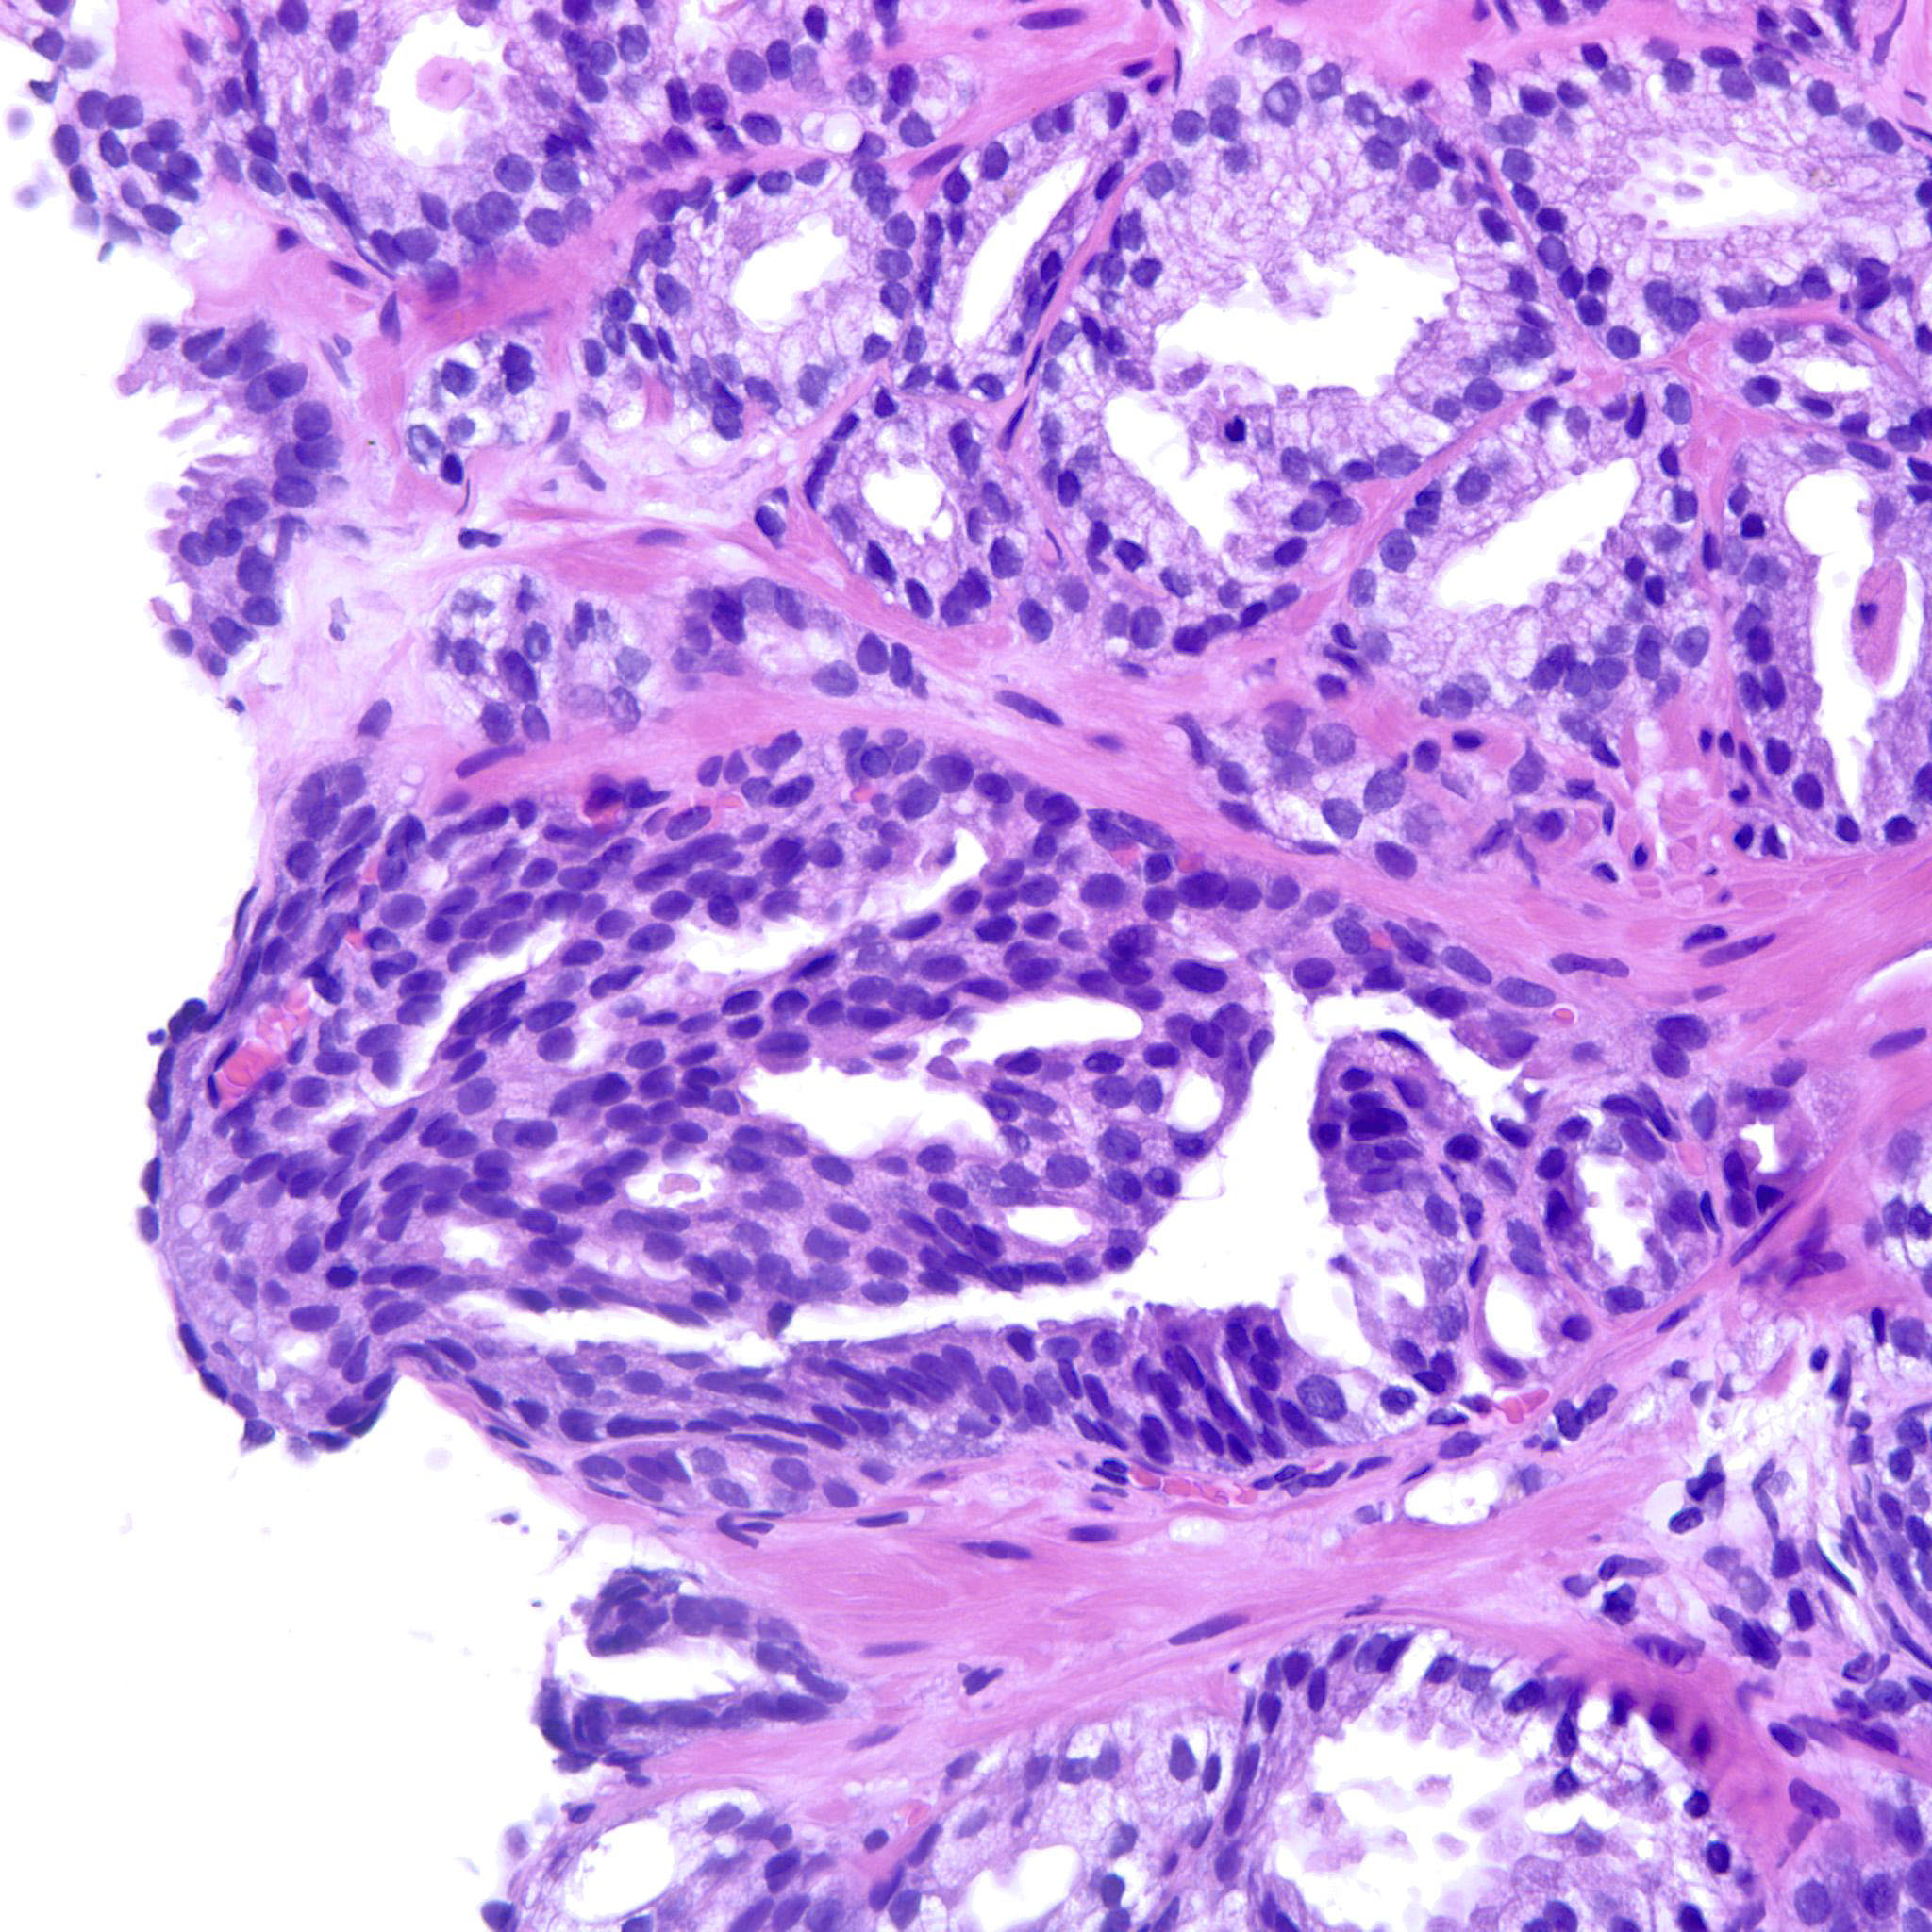

Prostate cancer grading

Case ID: 752